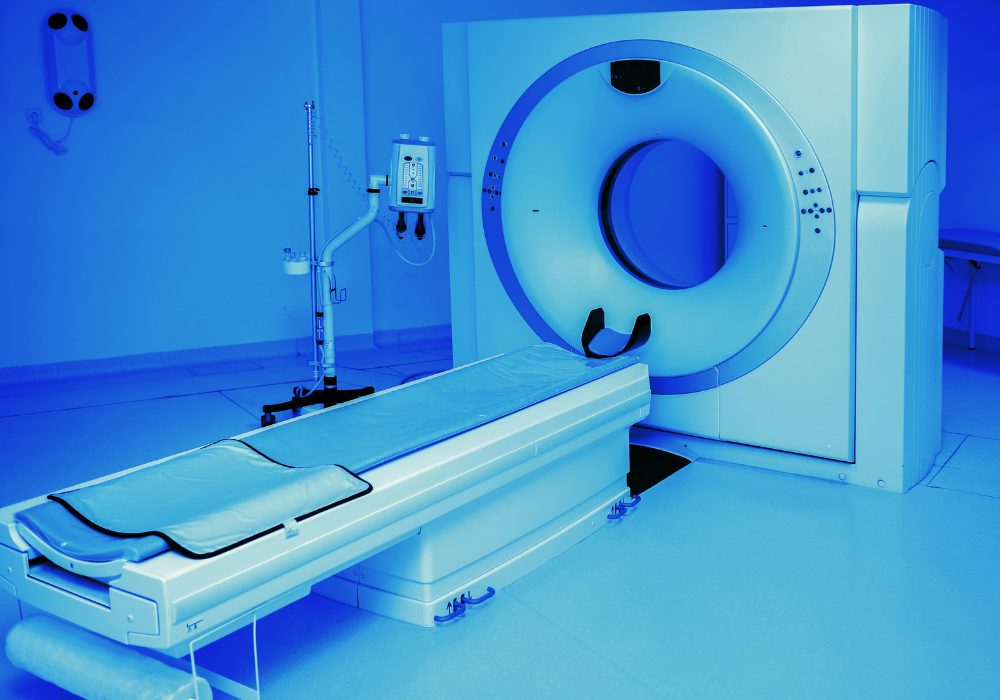

Immagini chiare, risposte rapide

Scanner all’avanguardia per il tuo benessere